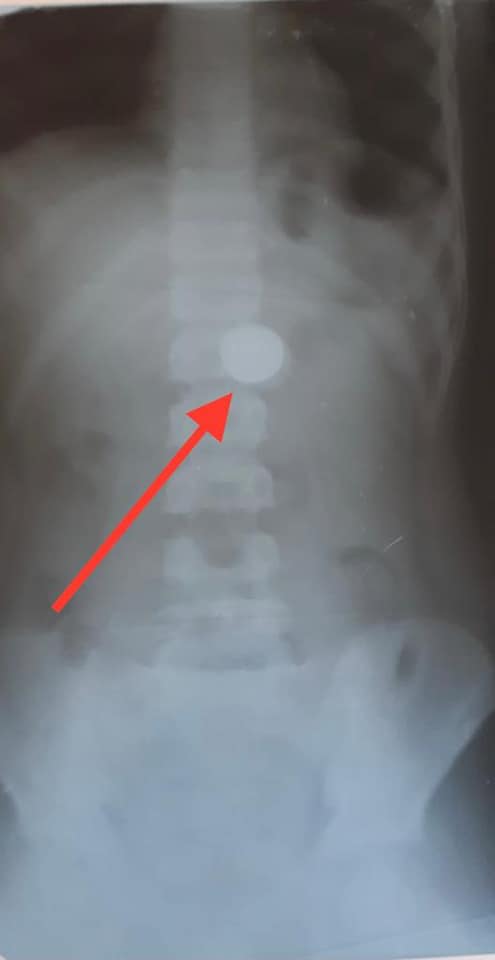

В Харьковскую областную детскую клиническую больницу №1 в один день поступили двое детей, которые проглотили монеты номиналом 1 гривна и 50 копеек. Об этом сообщили на странице медучреждения в Facebook.

Оба случая произошли 11 ноября.

Монеты извлекла заведующая отделением торако-абдоминальной хирургии врач-эндоскопист Наталья Романова. Теперь они станут экспонатами Музея извлеченных предметов.

"Закон парных случаев, как говорят в медицине. Разный возраст, но интерес к деньгам уже имеют", — написали сотрудники ХОДКБ №1.